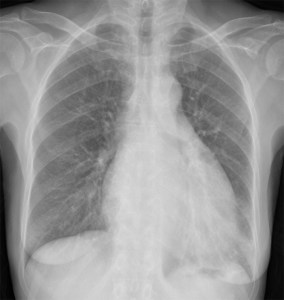

SIGNO DE LA SONDA NASOGÁSTRICA DESPLAZADA

El desplazamiento de la sonda nasogástrica a la derecha (que indica desplazamiento esofágico) en la radiografía de tórax, se ha descrito como el signo más fiable de rotura de la aorta torácica e indica la necesidad de realizar angioTC urgente. La primera imagen muestra el desplazamiento de la sonda (flechas verdes) así como un gran derrame pleural izquierdo (flechas naranjas).